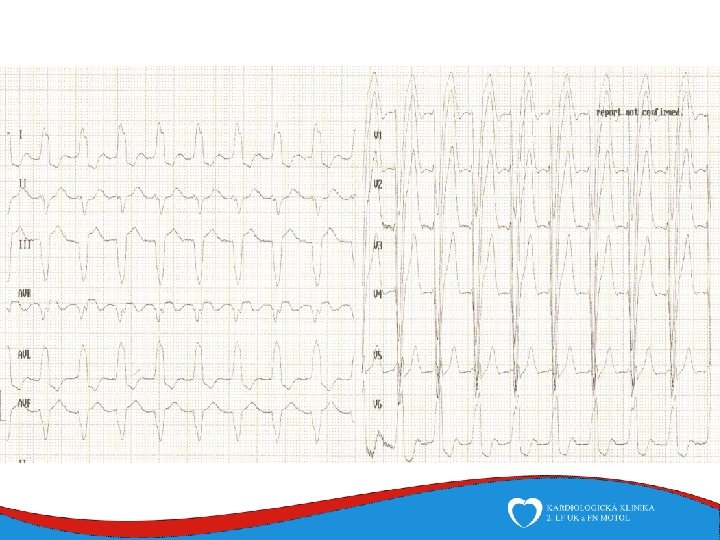

Diagnosis Family history Phisical examination ECG systolic murmur at the apex and lower left sternal border heterogenous LVH, patol. Q , QS, …. ECHO – golden standard MRI septal thickness more than 15 mm, papillary muscles hypertrophy, mitral anterior leaflet elongation, pressure gradient regions of myocarrdial fibrosis regions of late gadolinium enhancement (LGE) Stress test blood pressure responce ECG monitoring ventricular arrhythmia Selective coronarography

Work up ECG – typical - epsilon, neg. T v V 1 -V 3 - LBBB morphology VES ECHO MRI EMB

ECHO – anterior wall akinesis, LV EF 35%, mild mitral regurgitation, no dilation of right-sided chambers, no pericardial effusion